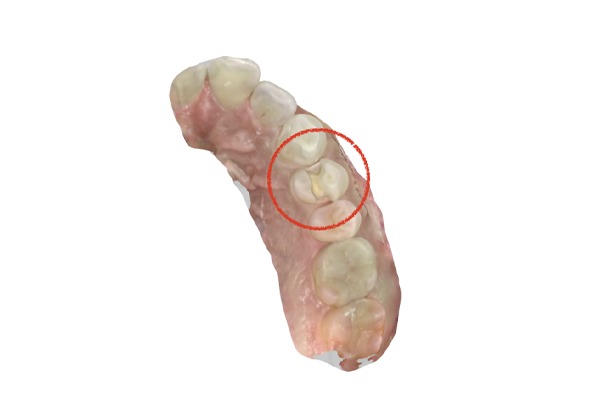

インレーの症例

インレー症例

治療前

途中経過

治療後

年齢・性別 43代・女性

主訴 パラジウムインレー2次カリエスの治療

治療内容 左上6セラミックインレー・

左上7ゴールドインレー

治療期間 10日程度

リスク・副作用 虫歯が深ければ、つけた後しみたり、痛みが出る可能性がある。 その場合は神経をとる処置をする。

歯ぎしり、くいしばりでセラミックインレーが割れることがある。

費用 セラミックインレー 55,000円

ゴールドインレー 88,000円